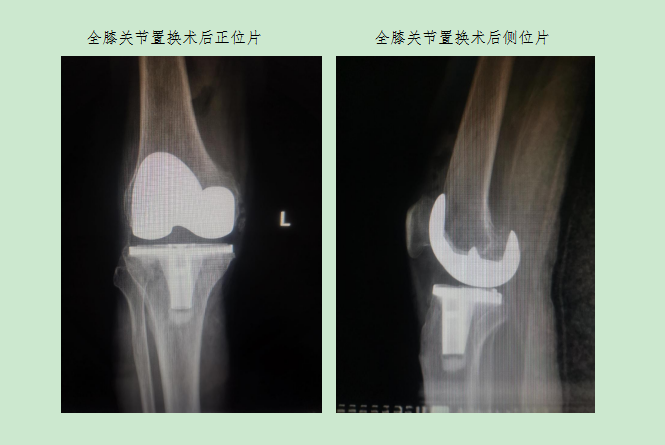

該患者入院后,完善相關(guān)檢查,蔡成成主任和主管醫(yī)生對(duì)患者全面評(píng)估后,制定出最佳的治療方案,鑒于患者右膝關(guān)節(jié)畸形尚不嚴(yán)重,活動(dòng)度尚可,計(jì)劃先行“左側(cè)全膝關(guān)節(jié)置換術(shù)”,待左膝關(guān)節(jié)傷口愈合、功能恢復(fù)后,再行“右側(cè)膝關(guān)節(jié)單髁置換術(shù)”,在醫(yī)護(hù)人員精心治療護(hù)理下,在患者及家屬配合下,順利為患者先后完成兩次手術(shù)治療。術(shù)后患者切口愈合良好,雙側(cè)膝關(guān)節(jié)屈伸活動(dòng)良好,兩次手術(shù)均在術(shù)后第二天下床活動(dòng),經(jīng)過(guò)為期三周的規(guī)范治療與功能鍛煉,該患者康復(fù)出院,出院時(shí)已擺脫輪椅自行下樓,完全恢復(fù)正常行動(dòng)。這是我科獨(dú)立成功完成的首例“人工膝關(guān)節(jié)單髁置換術(shù)”,標(biāo)志著我院骨科在關(guān)節(jié)置換領(lǐng)域向微創(chuàng)化、精準(zhǔn)化方向再次邁進(jìn)一步。

與全膝置換術(shù)相比,膝關(guān)節(jié)單髁置換術(shù)切口更小,膝關(guān)節(jié)內(nèi)損傷更小,患者術(shù)后恢復(fù)更快,大大縮短住院時(shí)間,節(jié)省住院費(fèi)用,而且由于膝關(guān)節(jié)的韌帶得到保留,患者術(shù)后的膝關(guān)節(jié)活動(dòng)度和本體感覺(jué)更好。目前,蘭州市第二人民醫(yī)院骨科已具備膝關(guān)節(jié)骨性關(guān)節(jié)炎的階梯化治療能力。科室可以為膝關(guān)節(jié)骨性關(guān)節(jié)炎患者提供系統(tǒng)治療方案,在指導(dǎo)功能鍛煉、藥物治療、關(guān)節(jié)鏡治療、截骨治療、單髁置換及全膝關(guān)節(jié)置換術(shù)中選擇最佳方案,讓患者足不出市即可享受到規(guī)范化、系統(tǒng)化診療服務(wù)。